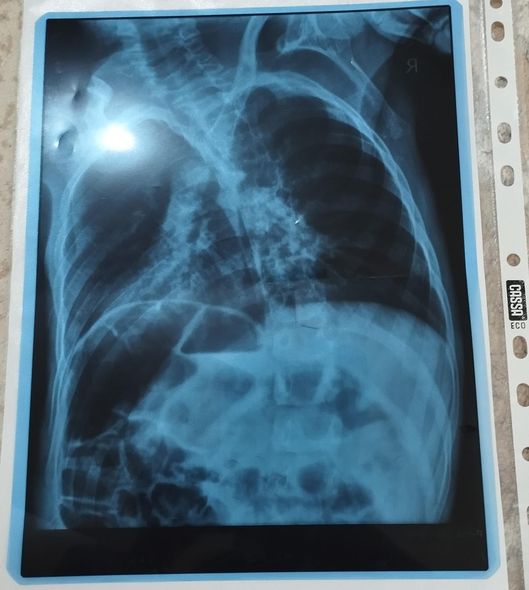

Nərminə Əzizova bildirib ki, Ömərə hazırda sətəlcəm diaqnozu qoyulub:

“Öməri soyuq havalarda qətiyyən çölə çıxarmırıq. Qış ərzində ancaq evdə olur. Evin istisinə o qədər öyrəşir ki, çox az müddətə çölə çıxanda xəstələnir. Həkimlər ona sətəlcəm diaqnozu qoyublar. Mənim Ömərlə birgə üç övladım var, Ömərin xəstəliyi bizi əldən salıb – heç nəyi çatdıra bilmirik. Ömərin müalicəsi üçün hazırda 600 manata ehtiyacımız var. Yardımsevər şəxslərdən bizə dəstək olmaqlarını xahiş edirəm”.